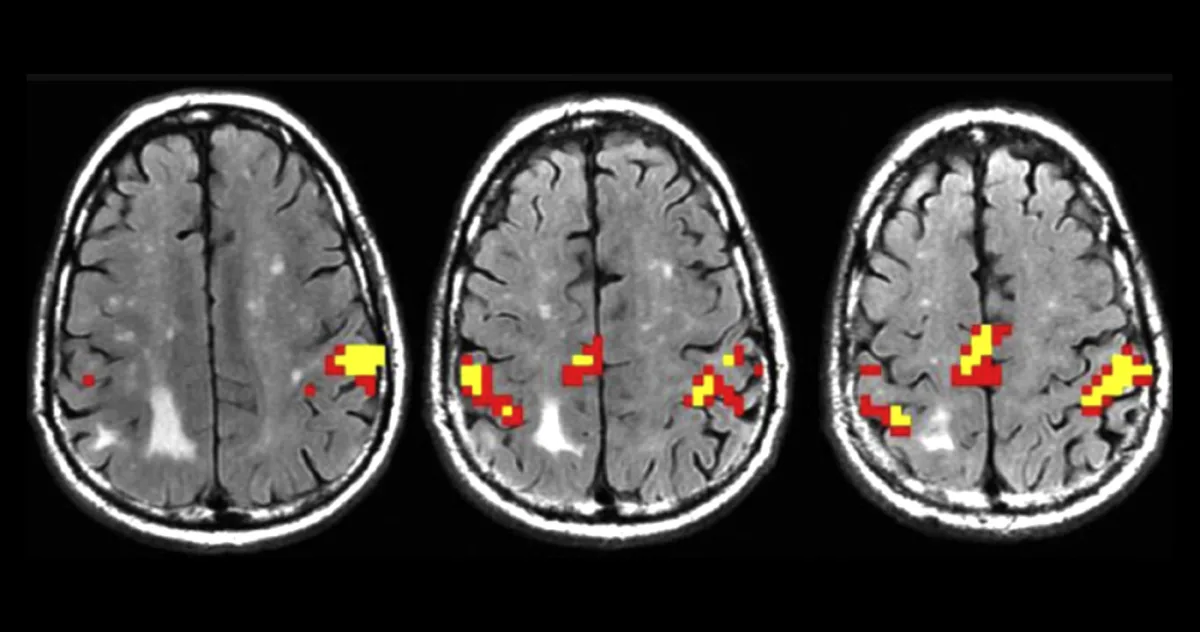

Echipa a folosit scanări RMN de înaltă rezoluție pe 61 de adulți cu vârste între 21 și 80 de ani, concentrându-se pe cortexul somatosenzorial primar. Cercetătorii au descoperit că această regiune este structurată ca o stivă de clătite, cu straturi delicate având funcții distincte.

Scanările au arătat că, deși unele straturi erau mai subțiri la persoanele în vârstă, așa cum era de așteptat, straturile din mijloc și cele superioare erau considerabil mai groase decât la participanții tineri.